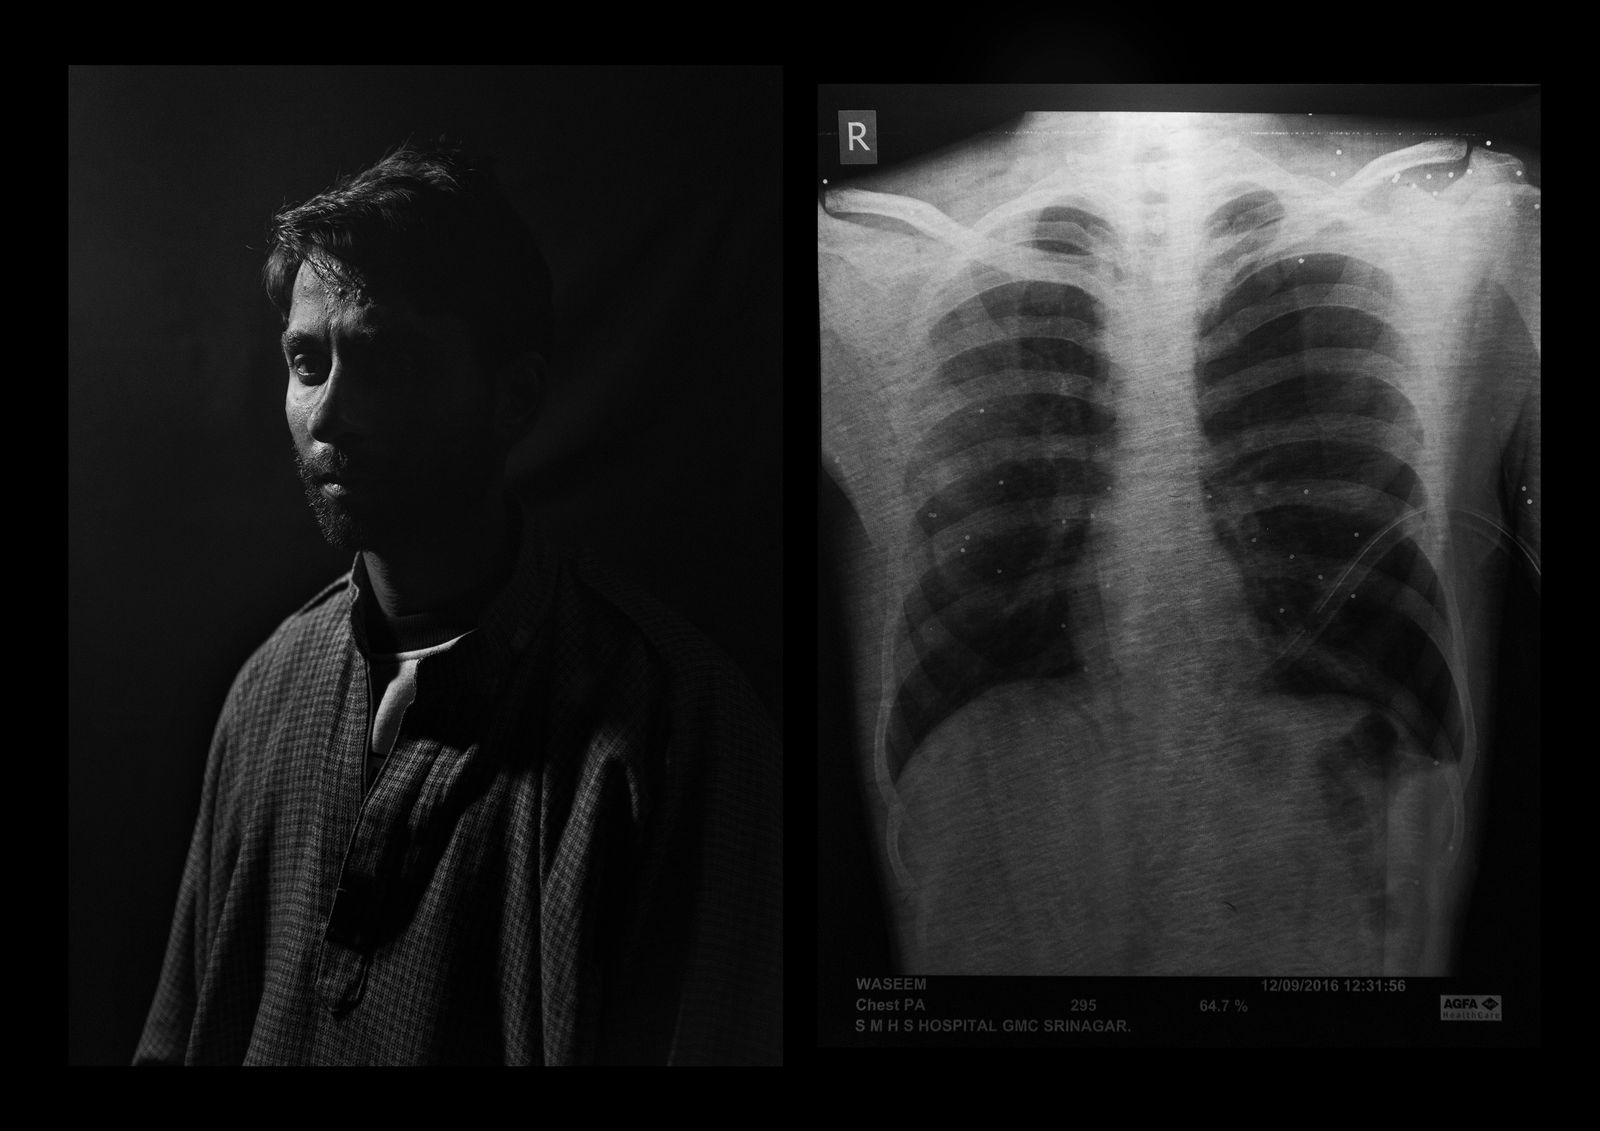

Shabkal Nazir Waseem, 25 years old, Bijbehera . “It was the day of Eid – the end of Ramadan – and i was watching the clashes happening on the national highway. The policemen saw me i was there and they targeted me. The security forces stopped all the vehicles, including the one carrying injured people. They took me to the hospital by a wood barrow. On the same day 4 person has lost their vision in Kashmir”. Nazir has received 100 pellets on the upper side of the body: 2 are in the right eye and 2 in the left eye. His visual capacity today is 10%.

© Camillo Pasquarelli - Image from the THE VALLEY OF SHADOWS photography project